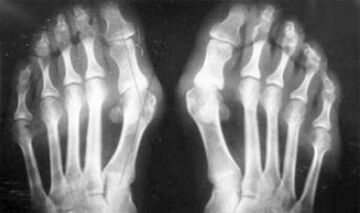

The difference between arthritis and finger and hand arthrosis is that the first disease is cured and the second is not.With arthritis, synovial shells and joint capsules are touched.

The loss of cartilage and bone tissue occurs only in the final stages in a neglected state.With arthrosis, cartilage tissue is first affected, and then bone, synovial membrane inflammation is secondary, that is, it develops with their background.